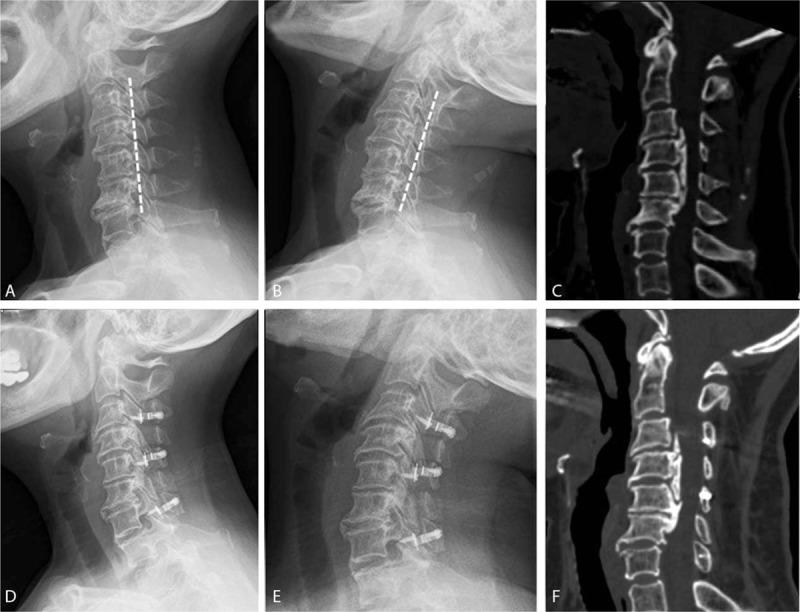

Patients with cervical ossification of the posterior longitudinal ligament (OPLL) who are K-line (-) are thought to have poor clinical outcomes after laminoplasty. The aim of this study is to compare the clinical results of patients with OPLL who were K-line (-) in the neck neutral position but K-line (+) in the neck extension position (NEP group) with patients with OPLL who were K-line (+) in the neck neutral position (NNP group).Retrospectively, 42 patients who underwent cervical laminoplasty for OPLL by our surgical group during 2012 and 2013 were reviewed and were followed for at least 2 years. The patients were divided into 2 groups according to K-line status. Standing plain radiographs of the cervical spine were obtained pre- and postoperatively. Cervical spine alignment parameters included the C2-7 Cobb angle and range of motion (ROM) measured on lateral radiographs. Clinical evaluation included pre- and postoperative JOA, NDI, and VAS scores.Ten patients were classified in the NEP group, and 32 patients were classified in the NNP group. Preoperatively, the OPLL involved segments were 4.10 ± 1.66 in the NEP group and 2.53 ± 1.16 in the NNP group (P = .005). The canal-occupying ratios were 58.40 ± 11.11% in the NEP group and 29.08 ± 11.38% in the NNP group (P < .001). The mean Cobb angle of both the groups had not changed significantly at the last follow-up. The mean cervical ROM of both the groups had decreased at the last follow-up. The mean JOA score of the NEP group improved significantly from 9.70 ± 2.16 to 12.50 ± 2.27 (P = .014). The mean JOA score of the NNP group improved significantly from 11.91 ± 1.69 to 14.93 ± 1.58 (P < .001). The mean JOA recovery rate was 32.71 ± 40.45% in the NEP group and 59.00 ± 33.80% in the NNP group (P = .036). The NDI scores of both groups were significantly decreased, and the VAS scores of both groups had not changed significantly at the last follow-up.Laminoplasty is a relatively effective and safe procedure for patients with K-line (-) in the neck neutral position but K-line (+) in the neck extension position. Instead of anterior surgery, we recommend laminoplasty for those patients with OPLL extending to 3 or more segments.